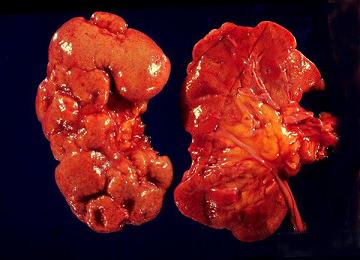

При остром пиелонефрите почка увеличивается в размерах, а ее капсула утолщается. При декапсуляции поверхность почки кровоточит и, как правило, имеют место явления перинефрита. На разрезе почки видны клиновидные участки желтоватой окраски, сужающиеся по направлению к гилюсу. Микроскопически в межуточной ткани определяются многочисленные периваскулярные инфильтраты с тенденцией к образованию абсцессов. Гной и бактерии из межуточной ткани проникают в просвет канальцев. Милиарные абсцессы в корковом веществе, считающиеся характерной чертой апостематозного нефрита, образуются в клубочках. Одновременно на почве эмболии капилляров вокруг канальцев могут возникать гнойнички и в мозговом веществе почки. Кроме того, в мозговом веществе почки образуются гнойные серо-желтые полоски, распространяющиеся вплоть до сосочков. При микроскопическом исследовании скопления лейкоцитов находят как в прямых канальцах, таки в окружающей ткани. Этот процесс может привести к некрозу сосочка, что, однако, более характерно для хронического пиелонефрита (Ю. А. Пытель, 1967). Причиной некроза сосочка считают нарушение кровоснабжения в нем. Мелкие абсцессы могут слиться, образуя гнойник.

По характеру патолого-анатомических изменений острый гнойный пиелонефрит может протекать с образованием множественных мелких гнойничков (апостем), локализующихся по всей почке, но с наибольшей концентрацией их в корковом слое, или множественных инфильтратов и гнойников, сконцентрированных в одном каком-либо участке почки (карбункул). Слияние нескольких апостем или расплавление карбункула ведет к образованию абцесса почки. В тех случаях, когда воспалительный отек или тромбоз сосудов резко нарушает кровоснабжение мальпигиевых пирамид, может наступить некроз почечных сосочков (некротический папиллит).